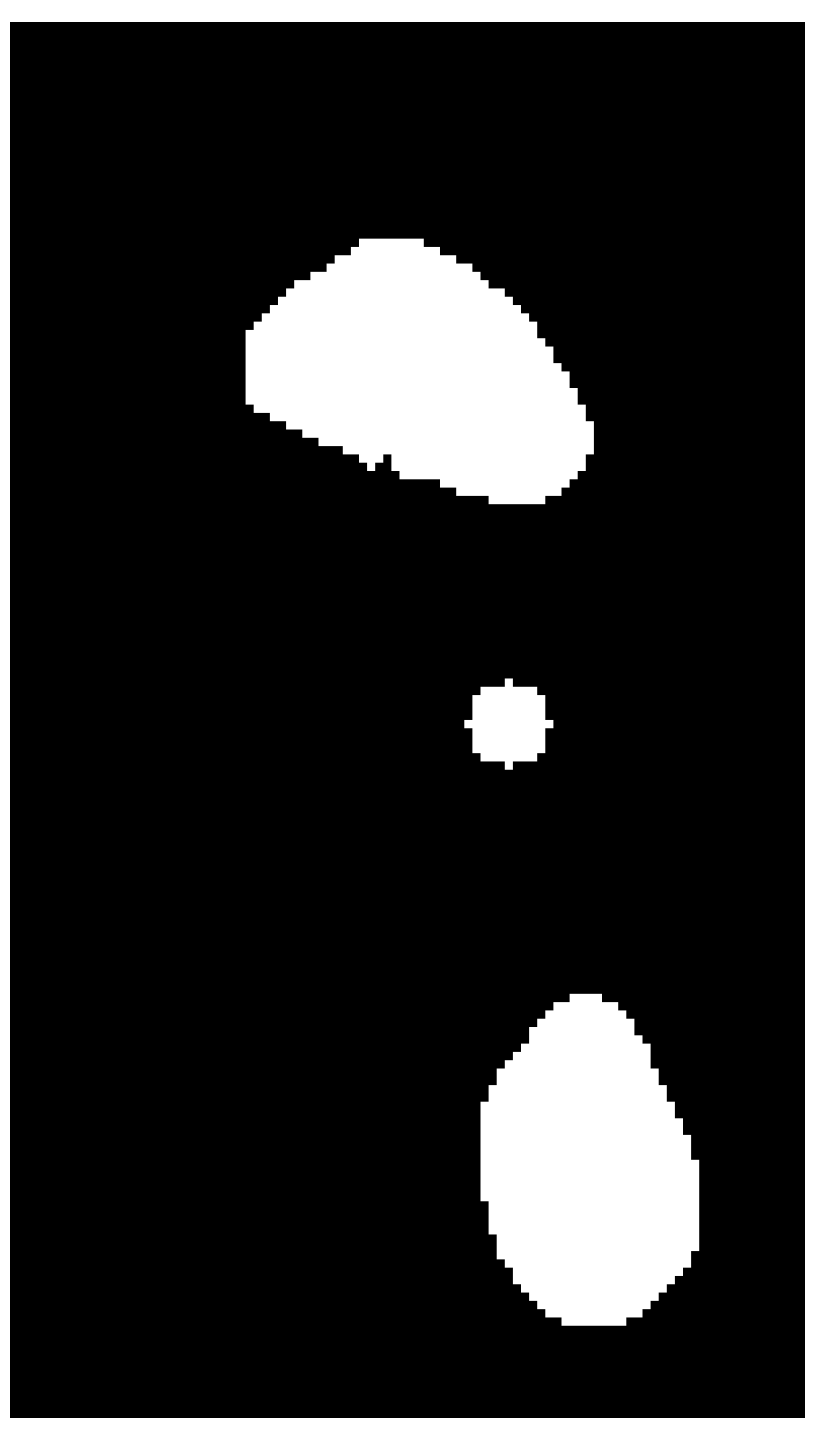

After removing the remaining traces of the contour and applying erosion and dilation operations, a black and white image was obtained (Figure 11). Erosion and dilation are morphological image-processing operations. Morphological image processing implies modification of geometric structures in the image. These operations are primarily defined for binary images but can also be used on grayscale images. Erosion removes the outermost layer of pixels in the structure, while dilation adds a layer of pixels to the structure [23].

The last step was to divide the height of the image into thirds with equal heights, and the area of each third of the footprint (Figure 12, white region) was calculated.

The surface values are used to calculate the foot arch index (AI) according to the formula:

A I = B A + B + C

The surface of the middle part of the foot is marked with B, the surface of the front part with A and the surface of the back of the foot with C. Therefore, AI represents the ratio of the area of the middle part of the foot to the area of the whole foot. It is a dimensionless quantity.

Based on the foot arch index (AI) value, foot deformities can be classified. If AI < 0.17, it is a hollow-foot-type deformity (pes cavus), and if AI > 0.28, it is a flat-feet-type deformity (pes planus). When 0.17 ≤ AI ≤ 0.28, it is a healthy foot without either of these two deformities [15,20].

Figure 11. Image after the application of morphological operations of erosion and dilatation.

Figure 12. Display of the thirds of the image that are equal in height to one another; front (left), middle (middle) and rear (right) parts of the foot.